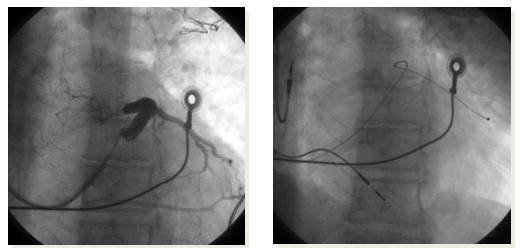

植入 CRT-D

入院前数天因室速CRT-D放电一次,后患者自觉胸闷不缓解入院,第二天突发意识丧失,呼之不应,经头颅CT排除脑出血,神经系统体格检查考虑大面积脑梗,急诊行脑血管造影,并急诊取栓

颈内动脉起始段完全闭塞